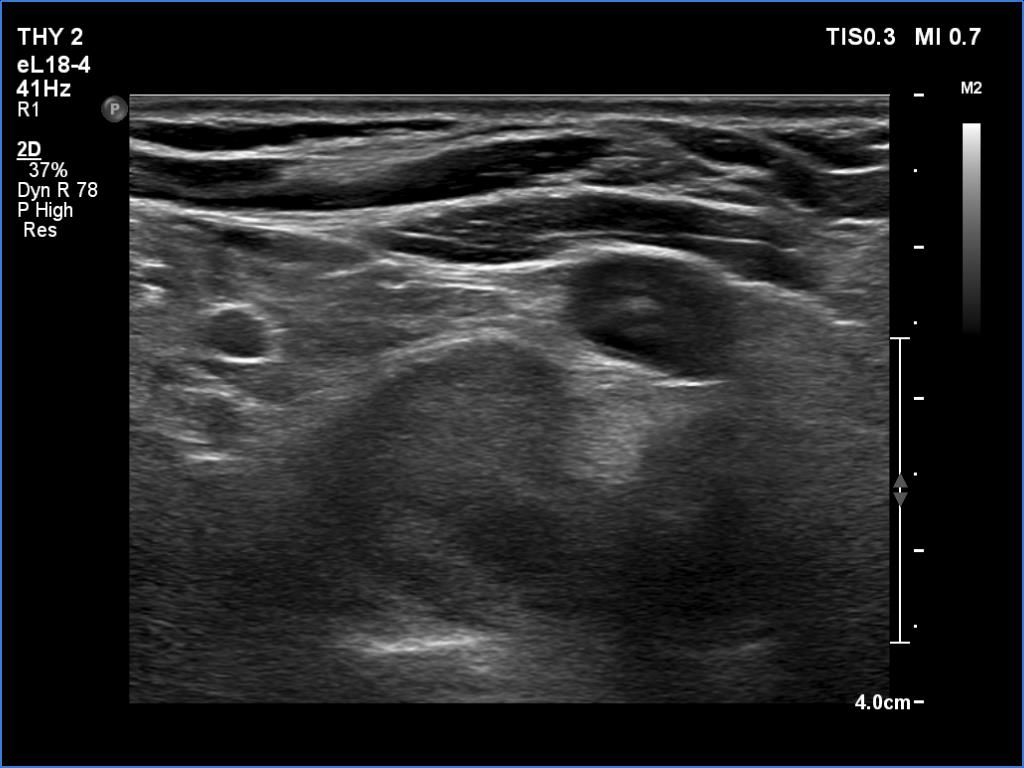

First examination (1st row of images)

Clinical presentation. A 51-year-old woman was referred for aspiration cytology of a thyroid nodule. She was examined because of depression and weight gain. (We met the patient in May 2020 during the COVID epidemic. Her endocrinologist did not meet the patient.)

Palpation: no abnormality.

Ultrasonography. The thyroid was echonormal and had several tiny hypoechoic areas and an echonormal nodule in the lower third of the right lobe. We did not find any lesion of clinical or oncological significance.